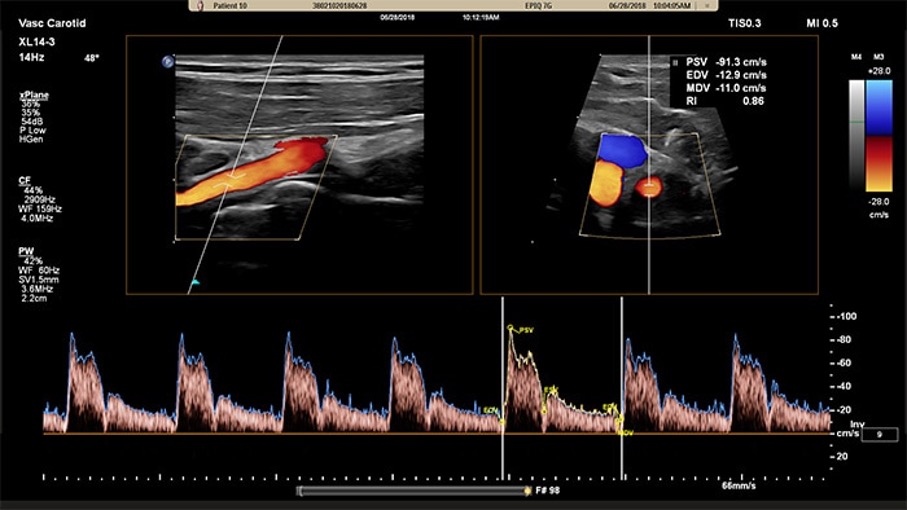

Ultraschall der hirnzuführenden Gefäße (Carotis-Doppler/ Duplex-Untersuchung)

- Diese Untersuchung dient der Beurteilung der hirnversorgenden Gefäße.

- Mit Hilfe dieser Untersuchung können zum Beispiel der Verlauf der Blutgefäße bis zum Eintritt in den Schädel, die Beschaffenheit der Gefäßinnenschicht, die Strömungsgeschwindigkeit des Blutes, Verengungen oder Verschlüsse der Hirngefäße z.B. durch das Vorhandensein gefährlicher Kalkablagerungen (sogenannter atherosklerotische Plaques) beurteilt und im Verlauf beobachtet werden. Sehr wichtig ist die Untersuchung beispielsweise für Patienten mit hohen Blutfetten, mit einem stattgehabten Schlaganfall oder nach Operationen an der Halsschlagader.